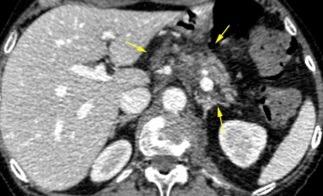

Ganglios retroperitoneales (flechas negras)

germinales del testículo izquierdo Nódulos pulmonares múltiples. (flechas verdes). Ganglios paratraqueales. (flechas amarillas). Dudoso ensanchamiento retrocrural (flechas negras)

Panda A et al. “Straddling Across Boundaries”. Thoracoabdominal Lesions: Spectrum and Pattern Approach. Curr Probl Diagn Radiol, 2015